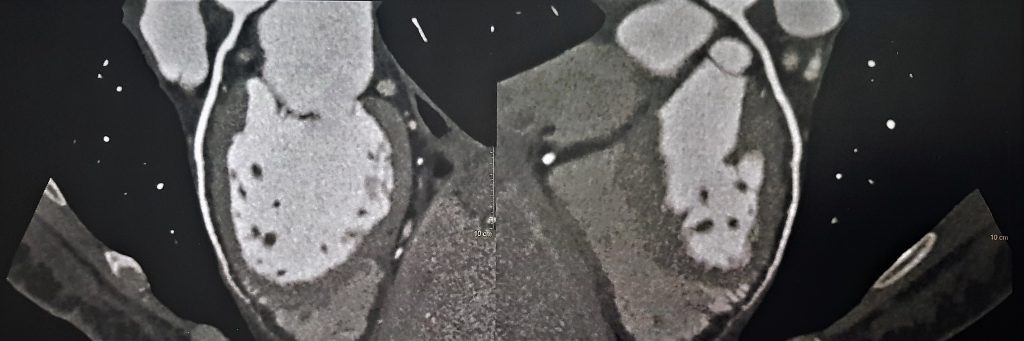

Debido a estos hallazgos se decidió evaluación mediante RMI y TAC. En la TAC multislice cardíaca se descartó la presencia de enfermedad coronaria.

TAC 1

TAC 2

TAC 3